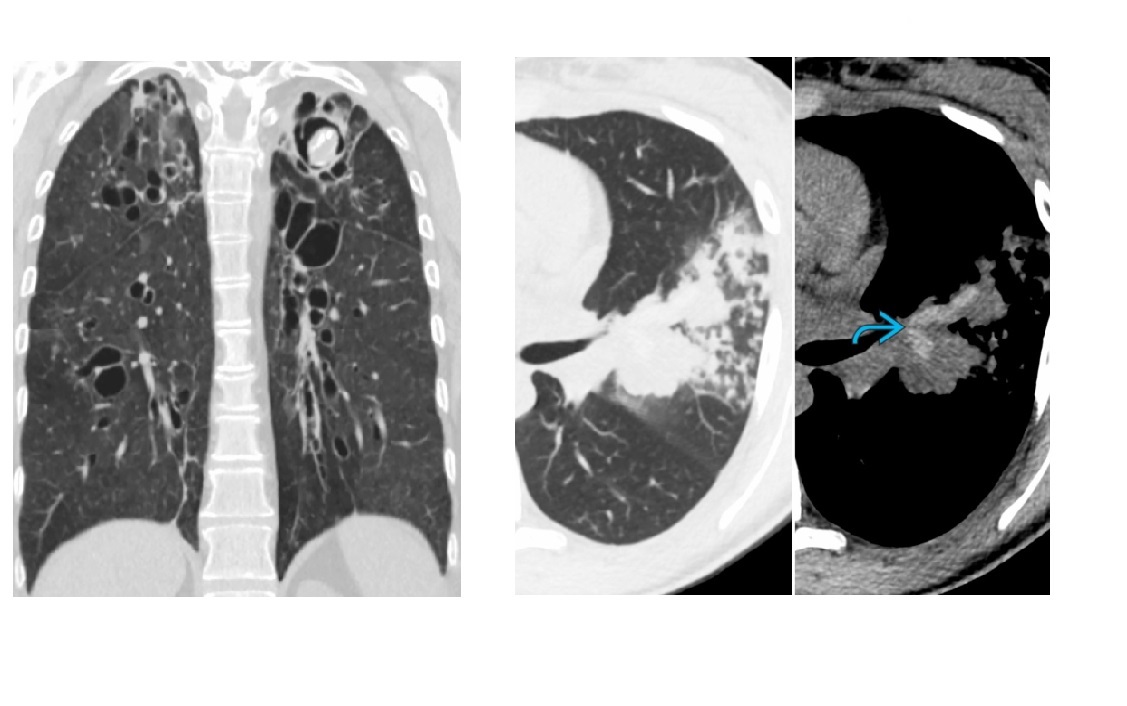

Angioinvasive aspergillosis

Halo sign

=Nodule/mass/consolidation surrounded by ground-glass opacity related to hemorrhage

Air crescent sign

=Crescent-shaped gas collection within nodule, mass, or consolidation

heralds improvement in the condition.

Aspergilloma

Nodule or mass within preexisting cavity

Lies dependent/ Intracavitary movement

Monod sign - gas that surrounds a mycetoma/aspergilloma in a pre-existing pulmonary cavity